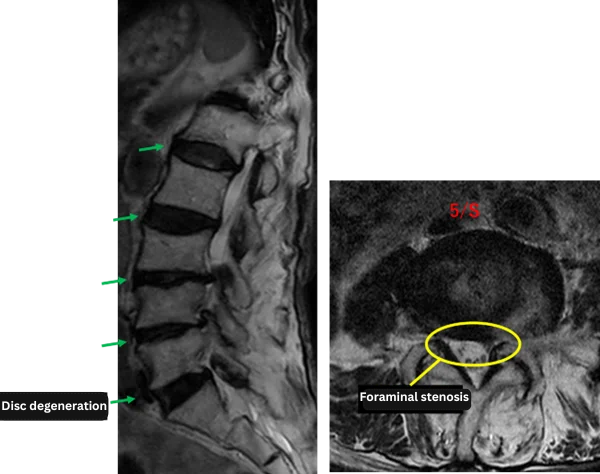

Imaging and findings

L1/2: Degeneration, bulging, right foraminal stenosis.

L2/3: Degeneration, bulging.

L3/4: Degeneration, bulging, left foraminal stenosis.

L4/5: Degeneration, bulging, left foraminal stenosis.

L5/S: Degeneration.

The above findings were also observed on the imaging.

Degeneration, disc bulging, and foraminal stenosis at L1/2, L2/3, L3/4, and L4/5 are considered the most likely causes of the patient’s primary symptoms.